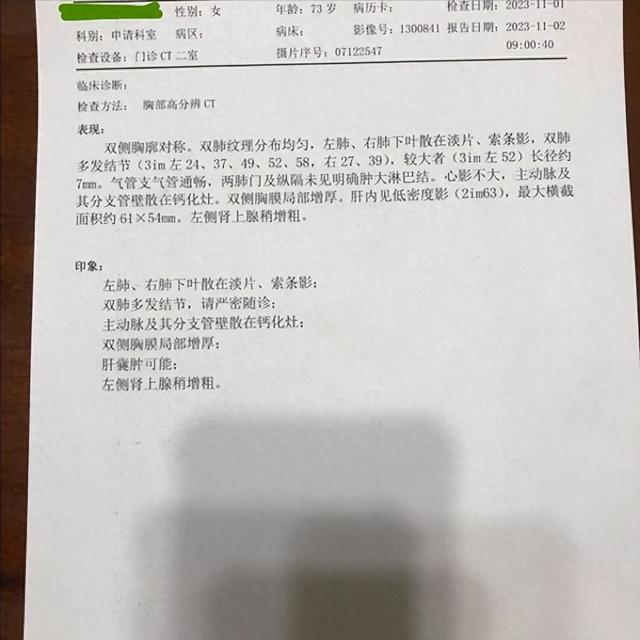

2023年11月1日我在北京也有高分辨CT的医院复查了CT。CT报告单写:双肺多发结节(省略)较大者(3im左52)长径约7mm。看主任助手帮我截图中右侧这2个结节的位置是新发吗?原右肺下叶7mm的结节我没看到。

2023年5月6日我在新桥做的CT,左肺上叶有2个1cm多大小的结节,2023年11月1日CT报告中没有描述这2个大结节,但在图像117/361和图像118/361的两张截图的上方这2个结节影还是可见。